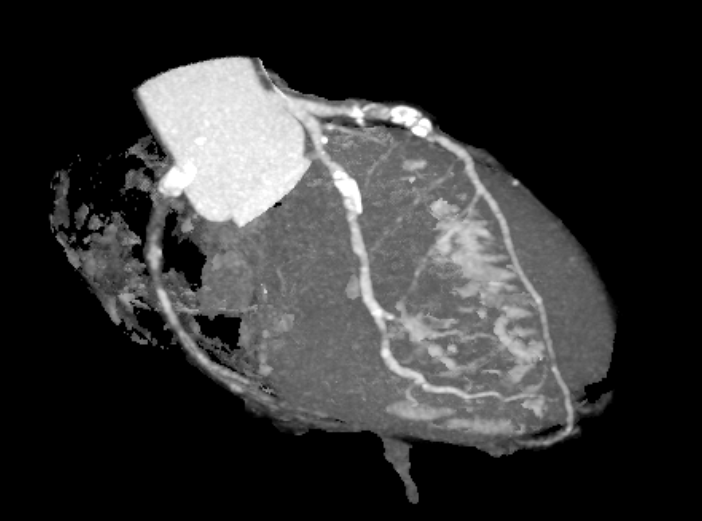

Coronary computed tomography angiography revealed a high calcium score of 1204.3 with focal occlusion and stenosis at the proximal LAD and proximal to mid RCA segments. Transthoracic echocardiography demonstrated preserved left ventricular systolic function (LVEF 61%) with mild hypokinesis of the basal anteroseptal wall.

Coronary angiography revealed three-vessel disease (SYNTAX score 29) with total occlusion of the proximal to mid LAD, 50% stenosis at the proximal LCX, and 70% stenosis at the distal LCX. The RCA showed chronic total occlusion from the proximal segment with collateral filling from both the LCX and LAD. The findings were consistent with acute anterior STEMI.

Because the patient presented with acute coronary syndrome, primary PCI was first performed for the culprit lesion, and a drug-eluting stent (DES) was implanted in the proximal LAD. A staged PCI with DES implantation to the proximal LCX was later performed. The initial antegrade attempt for RCA chronic total occlusion (CTO) failed despite wire escalations, as the guidewires could not cross the lesion. Considering the patient¡¯s intolerance and high contrast volume, the procedure was terminated. One month later, the patient was readmitted for complete revascularization. Antegrade wiring with a microcatheter and multiple guidewires (Fielder FC, ULTIMATEbros3, Conquest Pro) again failed to cross the RCA CTO. A retrograde approach using a SION wire via a septal collateral successfully reached the distal RCA. As the retrograde wire could not smoothly re-enter the true lumen, an antegrade wire was used to create a controlled subintimal hematoma, followed by the reverse CART technique. Anchoring balloon support then facilitated microcatheter advancement into the proximal RCA. The rendezvous technique achieved externalization with an ASAHI RG3 330 cm wire, and two Runthrough wires were advanced antegradely into the PDA and PL branches. After sequential balloon dilatation, two DESs (XIENCE Skypoint 2.75 ¡¿ 48 mm and 3.5 ¡¿ 38 mm) were deployed from the distal to the ostial RCA under IVUS guidance. Final angiography showed successful recanalization with TIMI 3 flow.